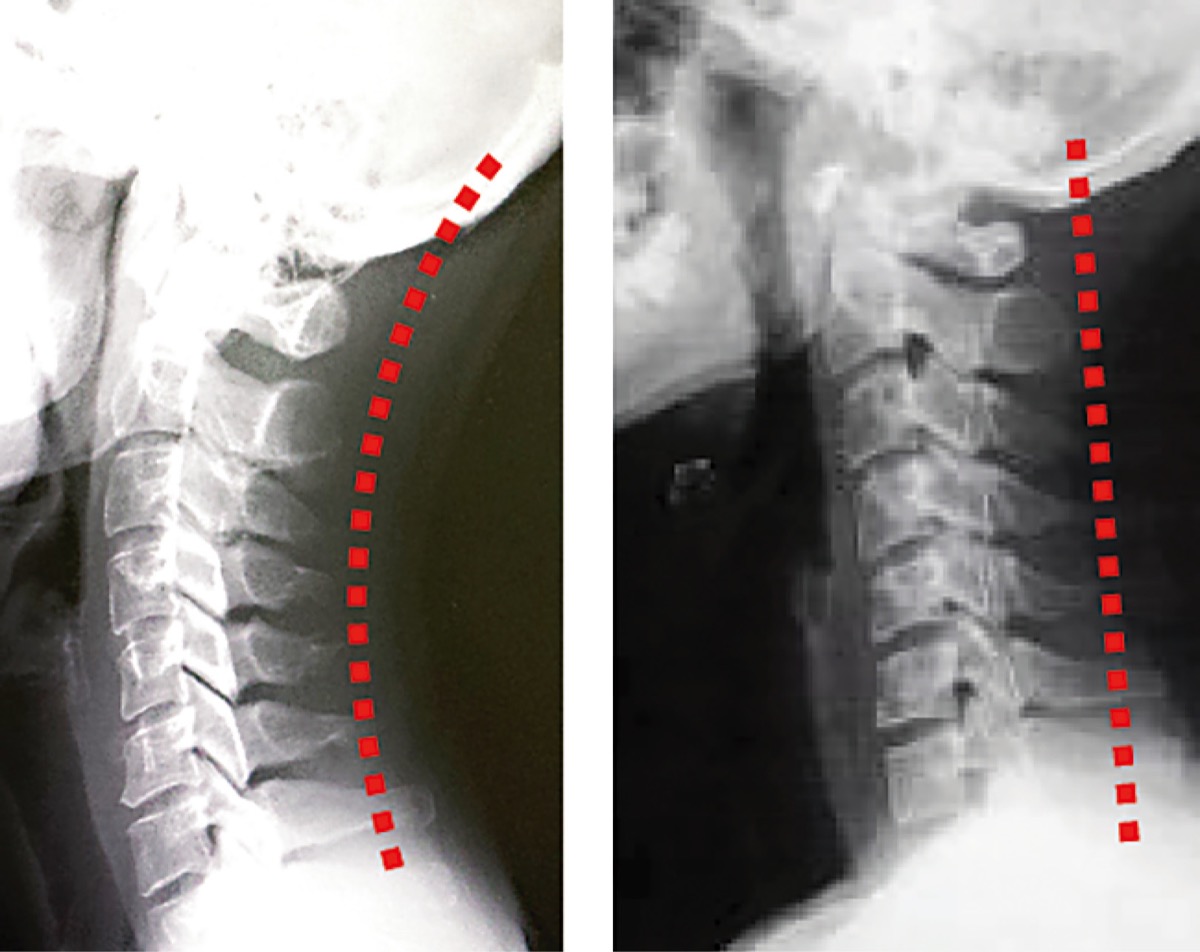

院長「座っているだけなのに痛む方もいます。スマホに向き合い、長時間うつむいた姿勢でいる事も要因でしょう。携帯ゲームで遊ぶ子が首や肩を痛めて来院する事も珍しくありません。本来頸椎は自然なカーブを描きますが『ストレートネック』は頸椎に負荷がかかります。頚椎の柔軟性が失われ頚椎が原因の神経症状が出ることもあります。